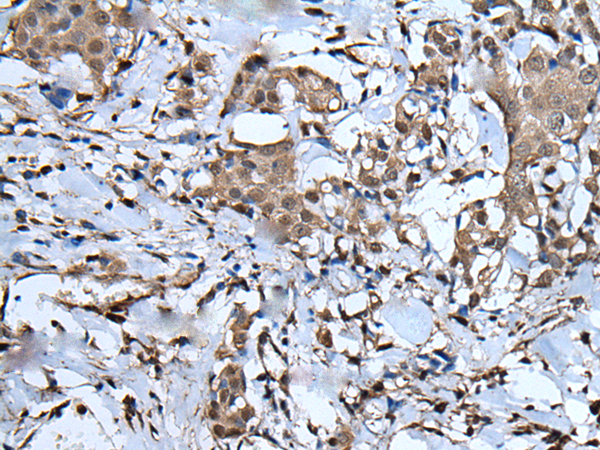

IHC positive control: |

Human liver cancer and human breast cancer |